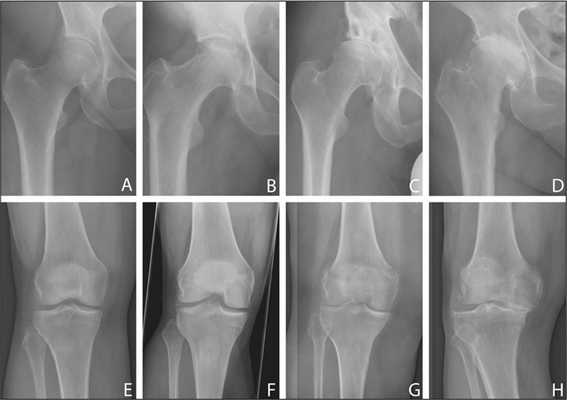

Рентгенография тазобедренного сустава

Тазобедренный сустав является сложным многоосным сочленением, которое выполняет сгибание/разгибание, отведение/приведение, пронацию и супинацию бёдер и принимает на себя серьёзную нагрузку. Любые нарушения в его функционировании не только приводят к серьёзному дискомфорту для человека, но и могут стать причиной развития серьёзных нарушений. Рентген тазобедренного сустава (ТБС) — это неинвазивный диагностический метод, ценность которого сложно переоценить.

Он нашёл широкое применение в разных областях медицины, включая травматологию, ревматологию, ортопедию, гнойную хирургию для диагностики заболеваний и последствий перенесённых травм, для определения объёма предстоящей операции или эффективности проведённого лечения. Процедура достаточно безопасна, высокоэффективна и проста, но при этом позволяет получить ценные данные о состоянии ТБС пациента.

Проведение рентгенографии ТБС

Стандартная рентгенография тазобедренного сустава проводится в 2-х проекциях. Помимо прямой используют вспомогательную, которая может быть боковой или задней косой, предусматривающей отведение бедра. Выбор, в данном случае, зависит от целей исследования и характера нарушений у пациента.

Рентгенография тазобедренного сустава в прямой проекции

Пациент принимает положение лёжа на спине, выпрямив нижние конечности. Стопа со стороны поражения должны быть повёрнута кнутри. Такое положение тела пациента обеспечивает хороший обзор медиальной части шейки бедра и даёт возможность определить медиальные переломы.

Рентгенография ТБС в косой проекции

Пациент принимает положение лёжа на спине, поражённая конечность согнута в колене и повёрнута кнаружи при косой проекции. В случае, если имеется подозрение на перелом бедра, локализующийся в области шейки, косую проекцию не используют, поскольку она может привести к смещению отломков кости и усугубить ситуацию.

Рентгенография ТБС в боковой проекции

Пациент принимает положение лёжа на спине, поражённая конечность согнута в колене и бедре под углом 90°. Под пятку ставят специальную подставку, трубку рентгена располагают сбоку со стороны здоровой ноги.